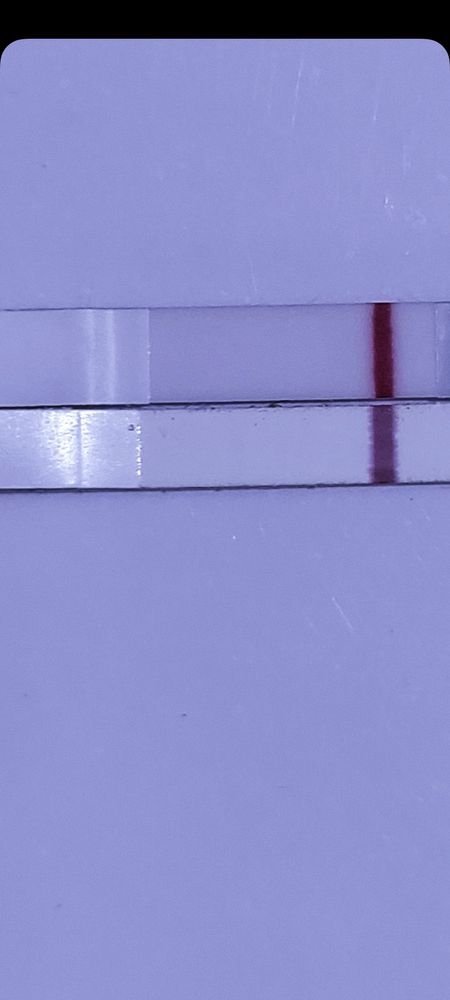

Я вижу на нижнем тесте тень. Верхний ещё мокрый Эви. Девочки я одна виду тень?

Я вижу на втором тень. Мне кажется, что даже за 4 дня уже должно быть видно

Tamara, не знаю как не видите😅 я на нижнем виду по разными углами. Причём не присматриваясь.